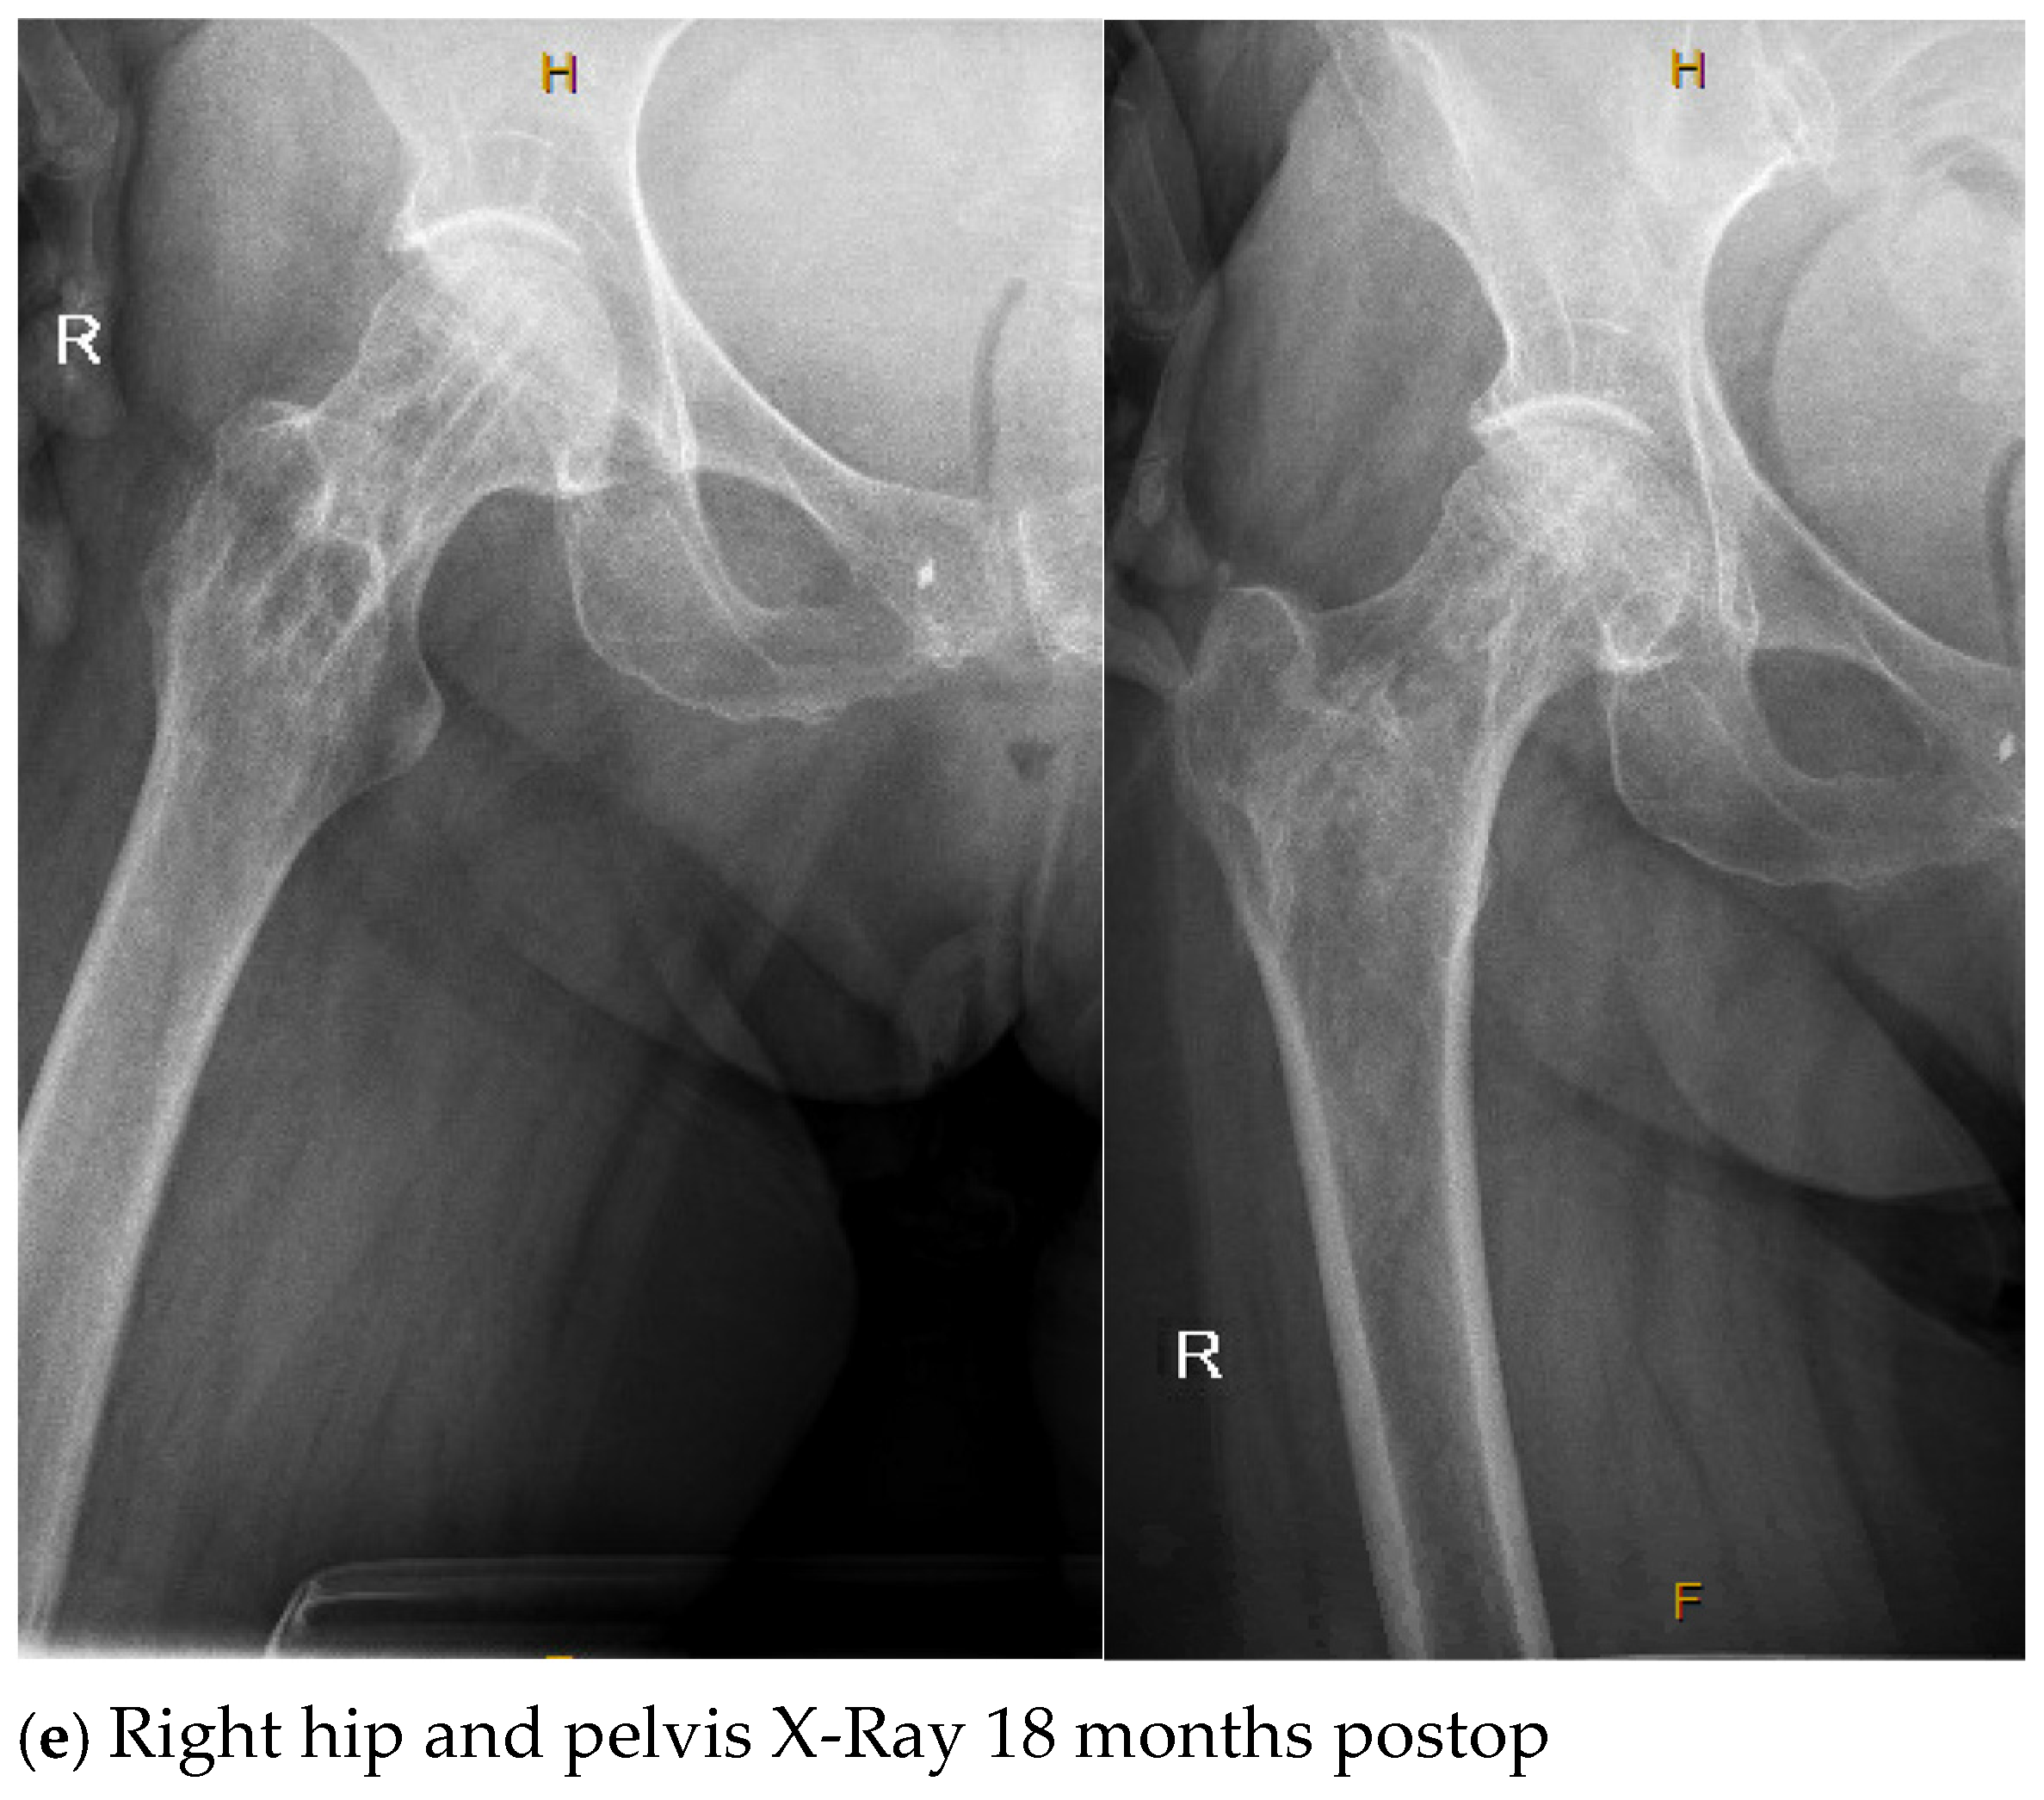

| 4. | 75 | F | Y | N | 20 | N | N | 17 | Right thigh and gluteal abscess with infected right femoral neck hardware and osteomyelitis |

| 4. | N | N | 14 | 4 | Y, clinical and lab | 107 | Negative |